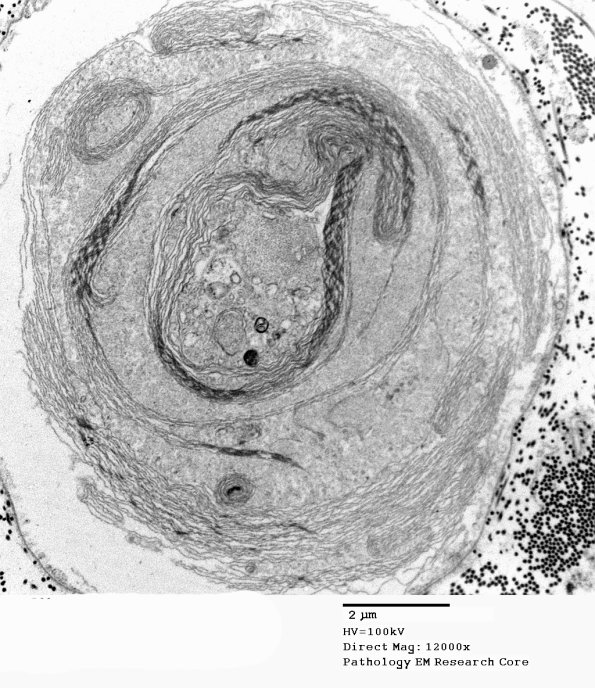

19E3 Artifact, myelin EM 032 - Copy

The pattern varies from axon to axon in the same nerve. (electron micrograph)